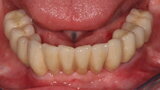

Fig. 11: Tissue level implants.